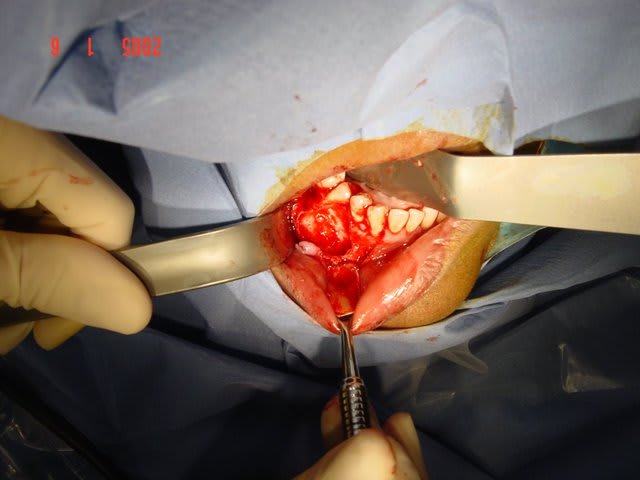

desole mais ls p^hotos sont pas top ;la panseuse est meilleur IBOD que photographe

j'ai demande au dentiste qui s'occupe de la patiente de realiser les endo avt la chir malgres le fait qu'elle avaient conservé leurs vitalité

a ce jour elle sont encore en place mai la 45 risque de sauter si dans 3 semiane je n'ai pas une meilleur stav*bilite transversale

ta envoyé a l'ana path?

juste pour la curiosité(ameloblastome???)

j'ai envoye

pas malin

pas de classfication particuliere

a priori je pense kyste epidermoide

Proche de la fracture md; bravo gal pour ton travail , merci pour ton cas intéressant ( les photos sont TB!!)

Comment as-tu gérer les rapports avec l'émergence du mentonnier au niveau de la région apicale de la 44 ?? Y'avait-il un risque de lésion ??

Pour le lambeau, tu as ruginé en t'arrêtant au dessus du foramen mentonnier ou tu as disséqué pour visualiser le nerf et le protéger ?

Pour l'énucléation, tu as décollé tout autour puis tiré à la fin sur la poche kystique sans cureter les parois osseuses dans la région du trou mentonnier?

si tu regarde le scanner tu verras que le foramen mentonnier a ete completement repousse au niveau du rebord basilaire par le kyste (desole je ne sai plu quelle numero de photo )

j'ai pu donc realiser un lambeau de pleine epaisseur de 43 a 47 avec incision de decharge en mesial de 43 puis arrive au niveau du rebor basilaire j'ai disseque en epaisseur partiel.

au niveau du kyste j'ai decolle la membrane kystique en mesial distal lingual vestibulair emais pas en apical puis avec une pince hemostaqtiue tu tires doucement et il veint en un gros morceau .

ensuite tu as un acces visuel sufisant pour te permettre de nettoyer la partie apical en respectant le nerf alveolaire

une fois visualise ce n'est pas difficile de ne pas l'abimer

c'est pas plus complique qu'une resection apicale